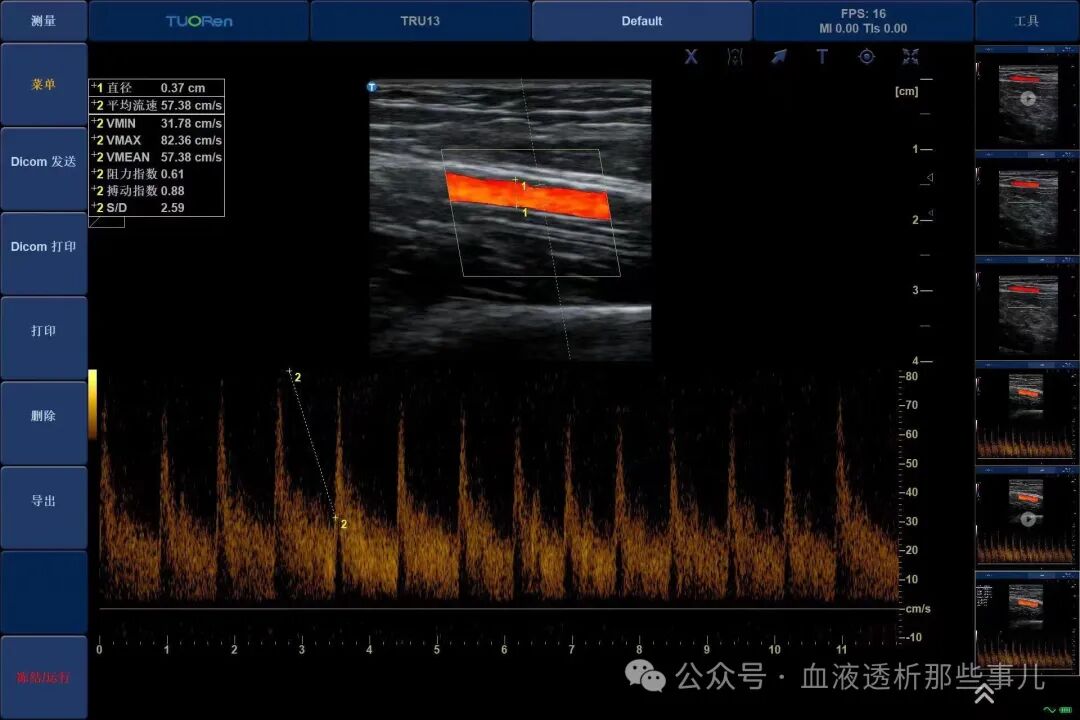

*测量内瘘血管血流量

内瘘血流量满足超声下血流量大于500 mL/min, 但不能满足血泵流量;